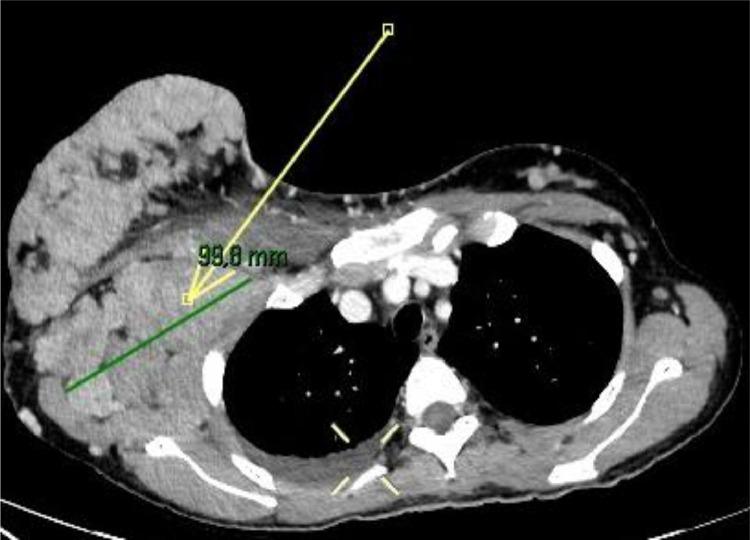

Pregnancy-associated breast cancer (PABC) presents unique challenges. This type of breast cancer is often more aggressive than that diagnosed in nonpregnant women, and its diagnosis is frequently delayed. Several factors contribute to this delay, including the physiological changes that occur during pregnancy, such as breast enlargement, breast tenderness and increased tissue density, which can mask early signs of malignancy. Additionally, a lack of awareness among healthcare providers can lead to symptoms being dismissed as normal pregnancy-related changes, and then being underestimated. Consequently, PABC is often diagnosed at more advanced stages, which can result in a poorer prognosis for the patient. This case study reports a 36-year-old woman in good general health, who received histological diagnosis of breast cancer during her pregnancy after presenting for self-detection of an enormous palpable breast mass. Prior to hospitalization, the patient had been treated with antibiotics in the mistaken belief that it was infectious mastitis; subsequently, considering the huge dimensions of the mass and the presence of lymph node metastases, neoadjuvant chemotherapy was started until induction of labor. Imaging techniques such as ultrasonography (and mammography as an adjunct) and nonenhanced MRI (due to potential toxicity of gadolinium to the fetus) can be used for staging maternal breast disease during pregnancy. A multidisciplinary approach which involves the radiologist, the breast surgeon, the oncologist and the gynecologist is fundamental to ensure the best prognostic outcomes for both the mother and the fetus.

妊娠相关乳腺癌(PABC)带来了独特的挑战。这种类型的乳腺癌往往比非妊娠女性所诊断出的乳腺癌更具侵袭性,而且其诊断常常被延迟。有几个因素导致了这种延迟,包括怀孕期间发生的生理变化,如乳房增大、乳房压痛和组织密度增加,这些变化可能掩盖恶性肿瘤的早期迹象。此外,医疗保健提供者缺乏认识可能导致症状被视为正常的妊娠相关变化而被忽视,进而被低估。因此,PABC往往在更晚期才被诊断出来,这可能导致患者预后较差。本病例报告了一名36岁总体健康状况良好的女性,她在怀孕期间自行发现一个可触及的巨大乳房肿块后接受了乳腺癌的组织学诊断。在住院之前,患者因误以为是感染性乳腺炎而接受了抗生素治疗;随后,考虑到肿块巨大且存在淋巴结转移,开始进行新辅助化疗直至引产。超声检查(以及作为辅助手段的乳腺X线摄影)和非增强MRI(由于钆对胎儿可能存在毒性)等成像技术可用于在怀孕期间对母体乳腺疾病进行分期。涉及放射科医生、乳腺外科医生、肿瘤内科医生和妇科医生的多学科方法对于确保母亲和胎儿获得最佳预后结果至关重要。